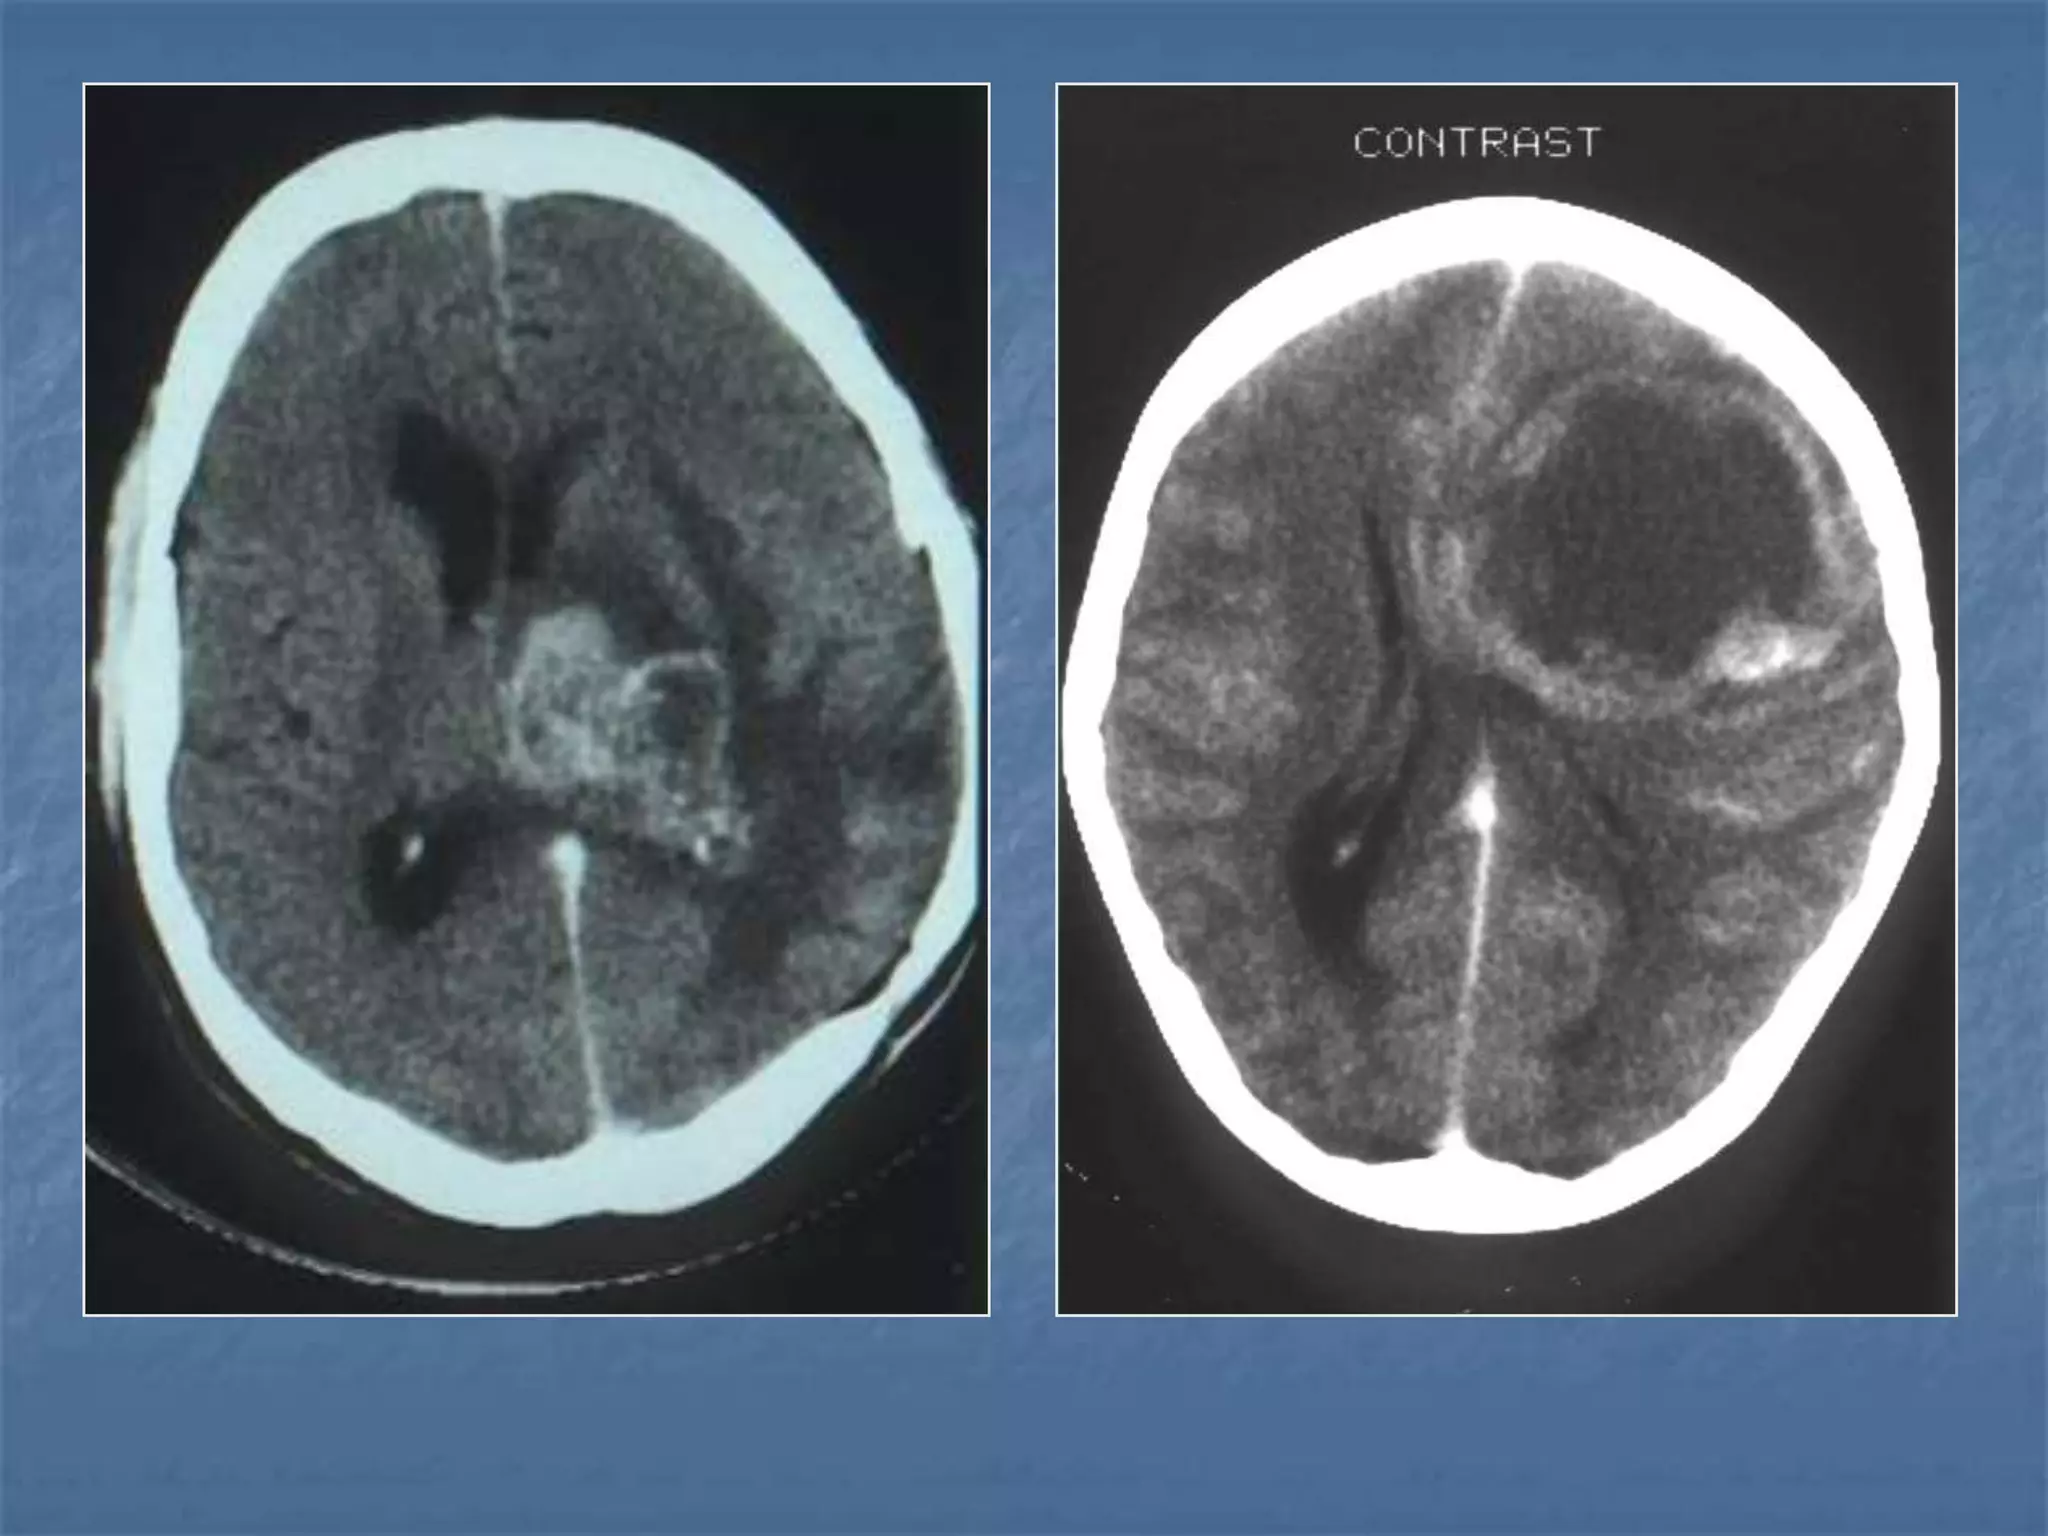

Hypertensive Hemorrhage

 Hypertensive hemorrhage accounts for

approximately 70-90% of non-traumatic primary

intracerebral hemorrhages. It is commonly due to

vasculopathy involving deep penetrating arteries

of the brain. Hypertensive hemorrhage has a

predilection for deep structures including the

thalamus, pons, cerebellum, and basal ganglia,

particularly the putamen and external capsule.

Thus, it often appears as a high-density

hemorrhage in the region of the basal ganglia.

Blood may extend into the ventricular system.

Intraventricular extension of the hematoma is

associated with a poor prognosis.